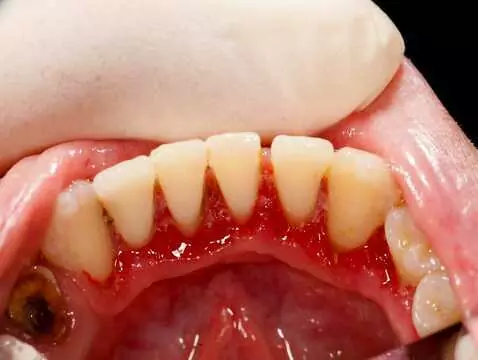

Gingivitis ist mit einer bakteriellen Infektion verbunden. Obwohl die Entzündung selbst nicht ansteckend ist, können die für ihre Entstehung verantwortlichen Bakterien von Mensch zu Mensch übertragen...

Unansehnlicher Zahnstein kann auf den Zähnen eines jeden Menschen entstehen. Ist er schädlich? Sollten wir ihn entfernen? Wie viel kostet er? Wir haben alle Ratschläge an einem Ort gesammelt.

Ein schönes und gesundes Lächeln ist der Traum von vielen von uns. Richtige Hygiene ist der erste Schritt zum Lächeln Ihrer Träume. Zahnsteinentfernung und Sandstrahlen werden in Zahnarztpraxen...